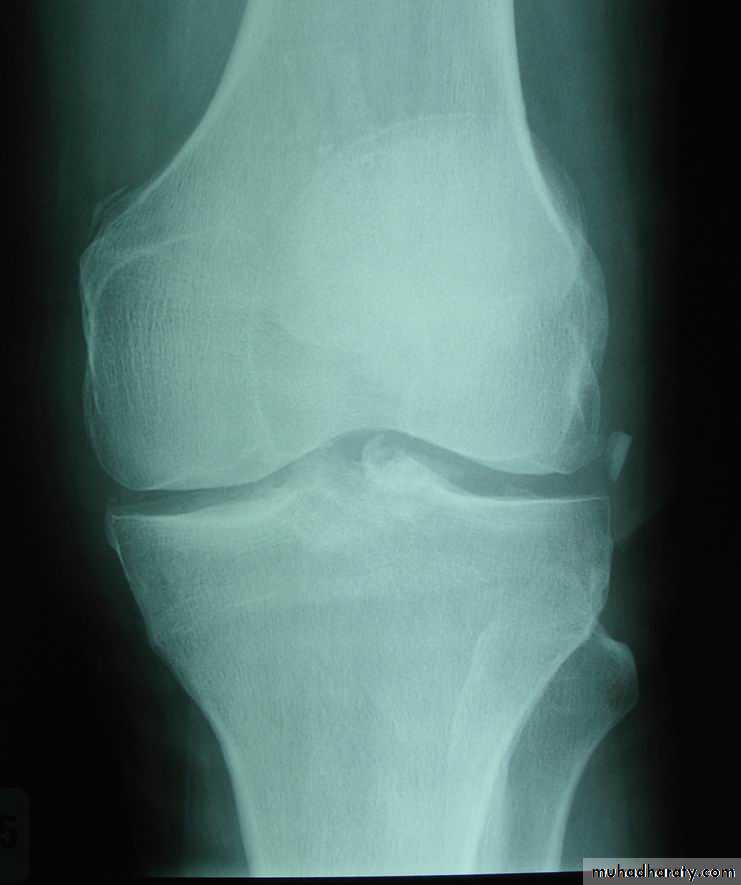

Genu varum & valgum

Genu varum = bow legGenu valgum = knock knee

On standingGenu varum : intercondylar distance > 6 cm

Genu valgum : intermalleolar distance > 8 cmCauses

XR : normal